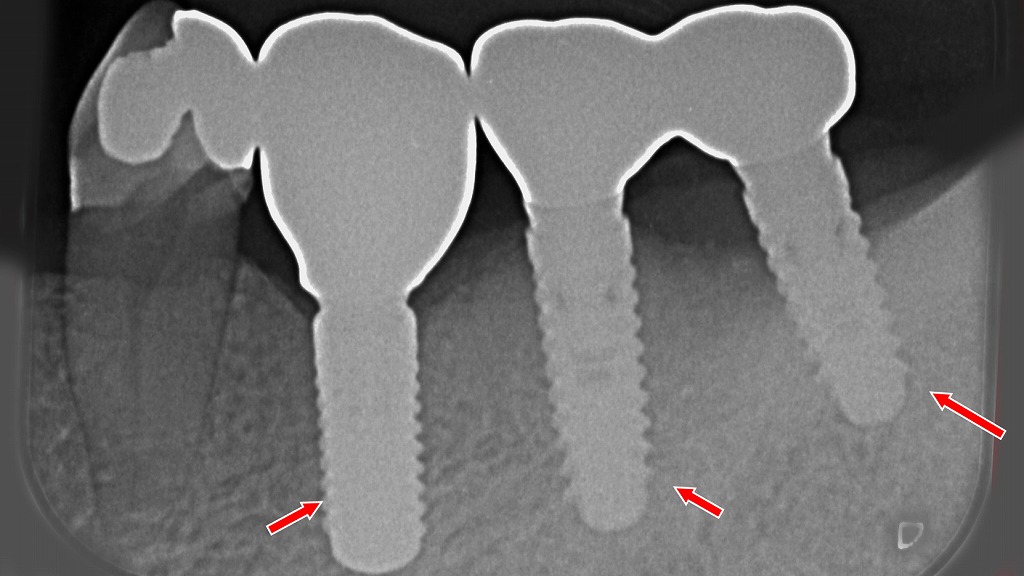

虫歯C2を放置すると、痛みがないまま進行し、最終的に抜歯が必要になることがあります。

抜歯後の治療方法には、周囲の歯を削って支える“ブリッジ”と、削らずに咬合機能を回復できる“インプラント”があります。

上顎では4・5・6番を自費ブリッジで補綴していますが、支台歯への負担増加や清掃性の低下といったリスクを伴います。一方、下顎では同部位を3本のインプラントで治療し、周囲の健康な歯を守りながら安定した咬合を再建しています。

治療選択は「残っている歯をどれだけ守れるか」を基準に検討することが重要です。